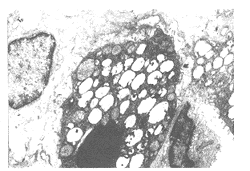

2.2.1 透射电镜显示ALI组肺泡腔狭窄、巨噬细胞活跃,上皮细胞增生,中性粒细胞浸润(见图4)。

图4 ALI组大鼠肺组织电镜(TEM×3 000)

2.3.3.1 透射电镜显示该组肺泡结构基本正常,上皮细胞完整,Ⅱ型上皮细胞内板层小体增加,肺泡Ⅱ型上皮细胞、中性粒细胞等多种细胞表现为核固缩、褪变(见图8)。

图8 912液组大鼠肺组织电镜(TEM×4 000)